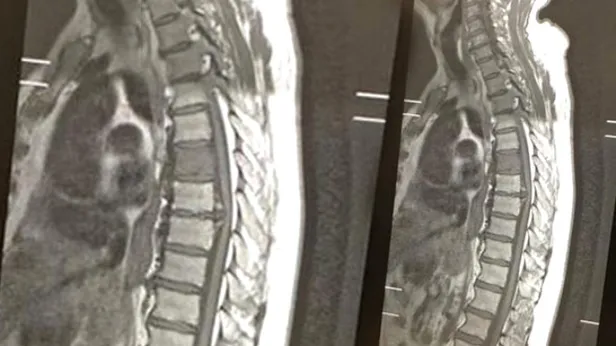

İngiltere'nin Liverpool kentinde akıllara durgunluk veren bir olay yaşandı. Daha önce yeme borusu kanseri tedavisi gören 70 yaşındaki Peter Cavanagh, 3 yılın ardından yendiği yemek borusu kanseriyle yeniden mücadele etmek zorunda kaldı. Omurgasını da etkileyen rahatsızlığı için röntgen çektiren adam, sonucu gördüğünde 50 yıllık eşi Tess ile birlikte gülmeye başladı.

Çünkü röntgen filminde 'cocker spaniel' cinsi bir köpeğin sureti gözüküyordu. Bu büyük bir tesadüften başka bir şey değildi. Görüntü hakkında şakalar yapan yaşlı adam, İngiltere gazetelerinde gündem oldu. Peter Cavanagh, "Ailemle köpeğin cinsinin beagle mı, spaniel mı olduğunu tartıştık ama bence kesinlikle spaniel. Burnu tam olarak, kanserin vücudumu etkilediği yerde" dedi.